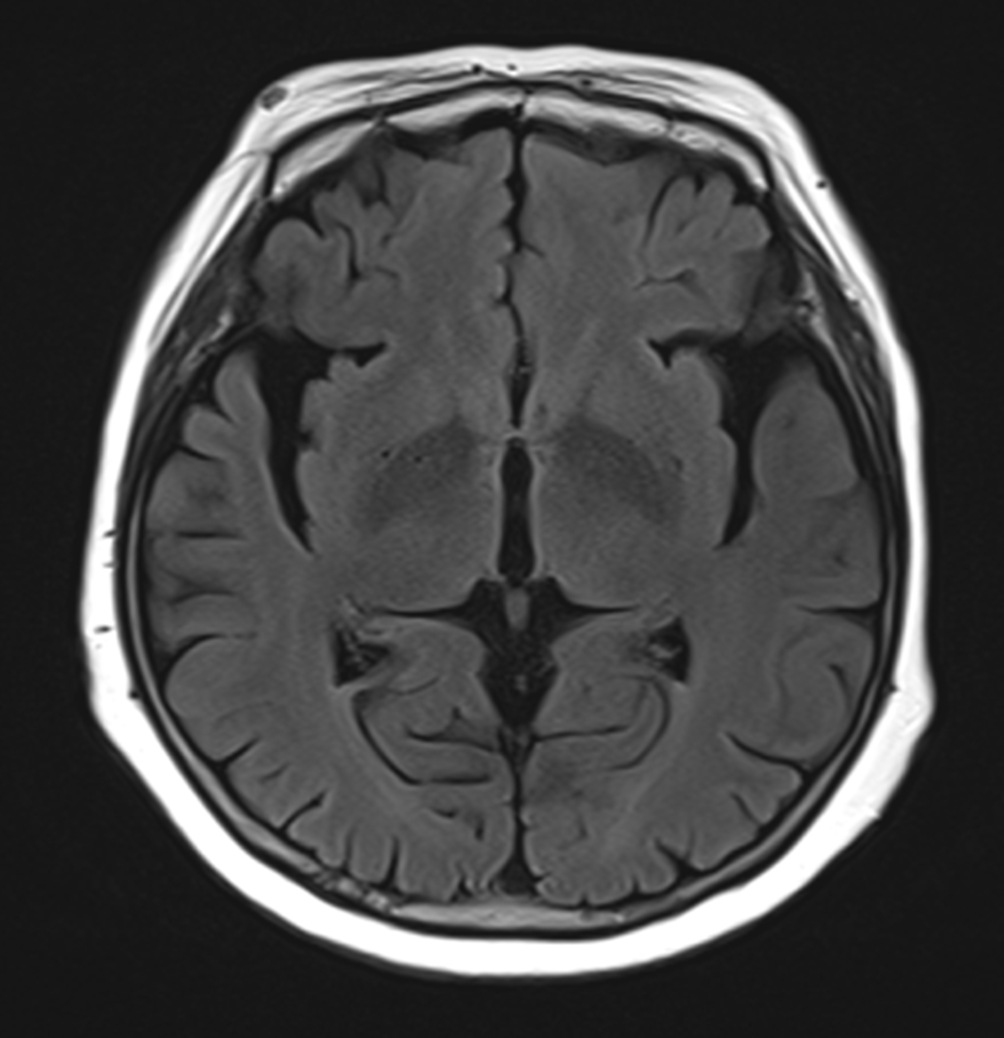

그림3.png 촬영 일시: 2025.03.29

<Fig 1. 뇌 MRI 영상>

파킨슨병 초기에는 MRI나 CT 같은 일반적인 영상검사로는

이상을 찾기 어려운 경우가 많아요.

특히 손떨림만 있는 초기 단계에서는 더욱 그렇죠.